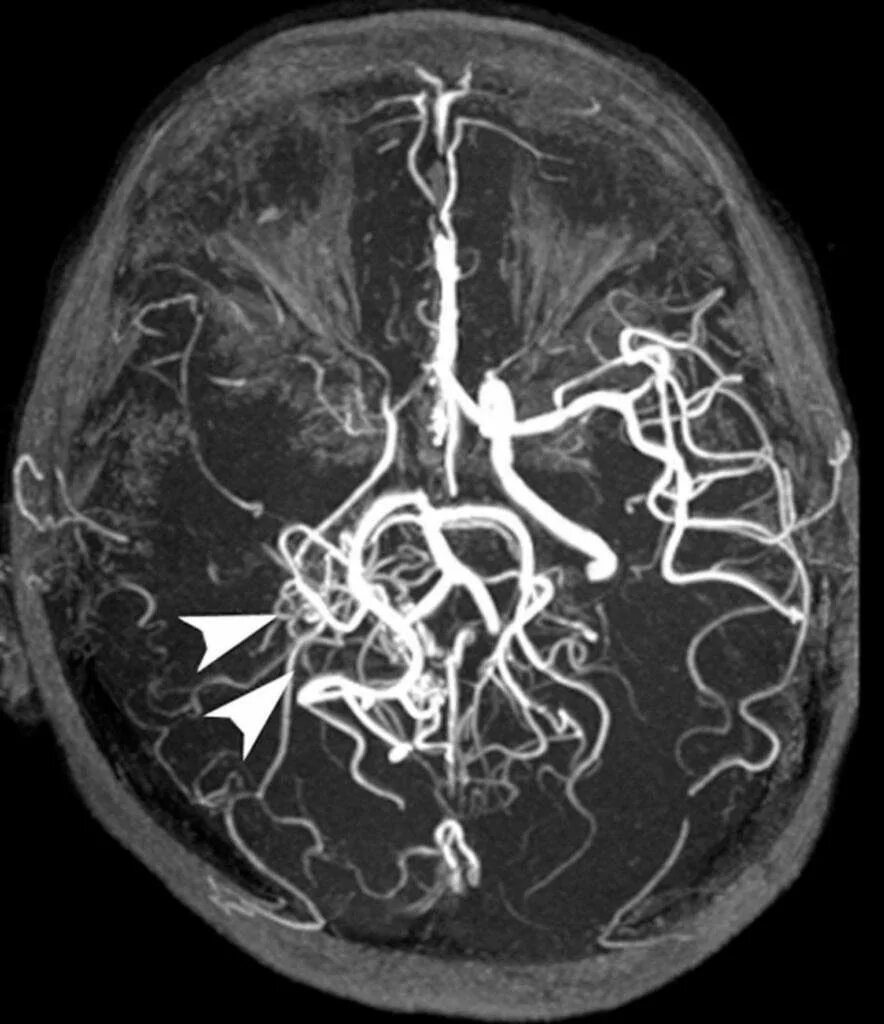

Мрт с контрастированием головного